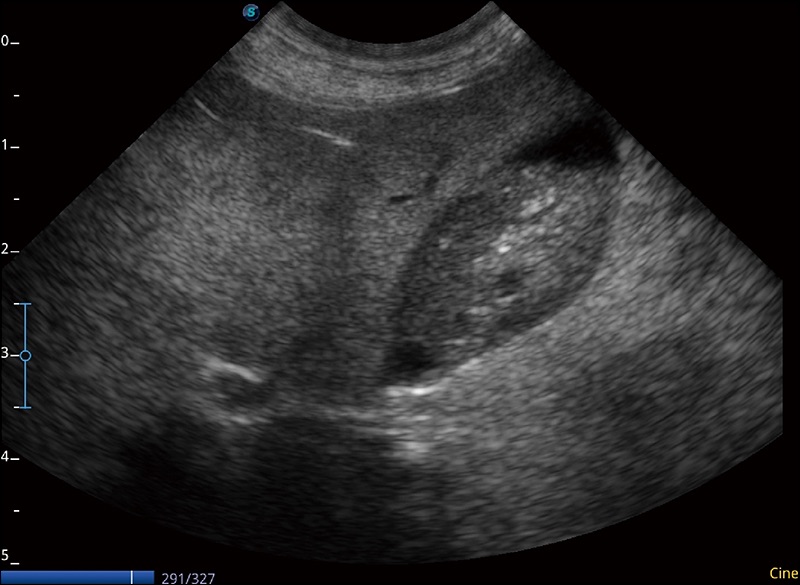

α1卓越的图像质量和便捷的工作流程,使每位宠物医生都能轻松扫查。其全面的兽用应用功能和紧凑型的结构设计,可以满足动物检查的多种需要。专业的预设检查模式和多领域测量软件包有助于为不同类型的动物提供检查, 让宠物医生能够出色的完成工作。